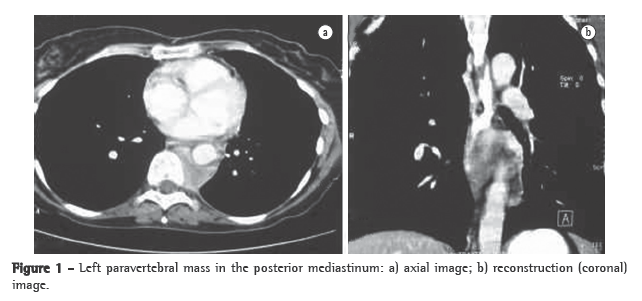

A 49-year-old female patient, who was a heavy smoker for 30 years (30 pack-years) and had chronic cough, sought medical assistance due to dyspnea and chest pain for 2 years. She was HIV negative. Her medical history included having been treated for pulmonary TB (4 years prior) and recurrent pneumonia (4 episodes in the last 4 years), as well as neck pain and lymphadenomegaly (2 years prior, with spontaneous resolution). A CT scan, without contrast enhancement, revealed a left paravertebral mass (diameter, 6.0 cm), located in the posterior mediastinum (Figure 1), and showed that the lungs were clear. The lesion was in close proximity to the descending aorta and bone structures, without signs of invasive growth. The patient was submitted to surgical excision of the mass. The surgical specimens included a 5.0-cm yellowish fragment and a 1.5-cm white nodule (identified as a para-aortic lymph node), together with lymph nodes from the left hilum and pulmonary ligament. Microscopically, the larger fragment and the para-aortic lymph node exhibited fibrous and adipose tissue, together with chronic inflammatory infiltrate in which there was a predominance of mature lymphocytes and plasma cells. Large histiocytes with pale cytoplasm were a common finding, as were sparse areas of aggregation and images suggestive of emperipolesis (Figure 2a). These initial findings were suggestive of a diagnosis of RDD, and immunohistochemistry was recommended for confirmation. The immunohistochemical procedures were performed at a referral laboratory and supported this diagnosis, based on the analysis of the large histiocytes, in which we observed expression of S-100 (Figure 2b) and CD68, although no CD1a reactivity was detected. Kappa and lambda chains were expressed in plasma cells, whereas CD20 and CD3 were expressed in mature lymphocytes. There was no residual lymphoid tissue in the largest fragment or in the para-aortic nodule. The lymph nodes resected from the left hilum and pulmonary ligament were unaffected. No additional treatment was administered after surgery. During a 12-month follow-up period, the patient complained of mild cough and chest pain. Periodic imaging tests showed no sign of recurrence, and no postoperative cervical lymphadenomegaly was detected. Pulmonary function tests (spirometry) performed at the time of tumor diagnosis and six months after tumor removal revealed a mild restrictive pattern.